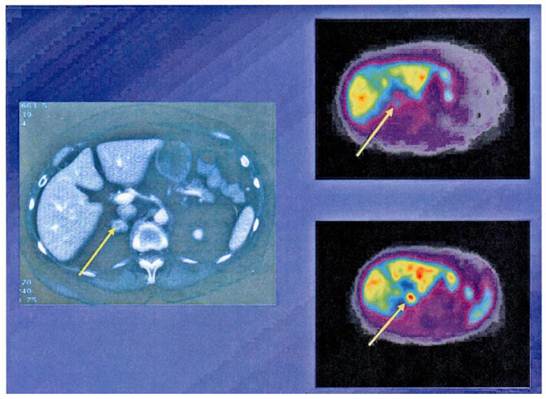

Figure 2

68Ga-DOTA-Octreotide PET/CT scanning with a patient with malignant carcinoid tumor showing multiple lymph node metastases as well as large liver metastases.

The ability to tag somatostatin analogs with 68Ga has revolutionized the role of PET in diagnosis, staging and therapy monitoring of patients with receptor positive NETs. One of the advantages of the 68Ga-DOTANOC/DOTATOC PET or PET/CT study over 111In-Octreotide scintigraphy is better visualisation of lesions which are difficult to be seen on planar or SPECT imaging.[11-13] 68Ga- DOTATOC PET appears to be superior especially in detecting small tumors or tumors bearing only low density of SRS (Figure 2). In general 68Ga-DOTATOC or DOTANOC PET is able to pick up many lesions which could not be picked up by CT-scan. It is of significance in therapy monitoring and is a useful adjunct in deciding the amount of radioactivity to be administered for PRRT. In an intraindividual study comparing the diagnostic efficacy of 68Ga-DOTANOC and 68Ga-DOTATATE, 68Ga-DOTANOC is superior to 68Ga-DOTATATE in terms of sensitivity.[14] In summary, among several advantages of 68Ga-somatostatin analogs over 111In-DTPA Octreotide scintigraphy higher sensitivity is present.[15] It is a one-stop procedure, the patient can leave the clinic after 1 hour instead of coming back 4 and 24 hours for scanning. It will also in the future be cheaper than SRS.